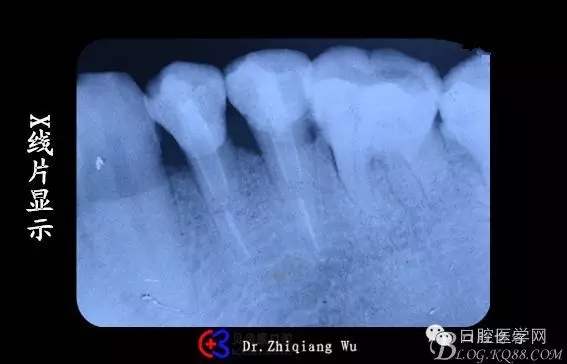

X線(xiàn)片顯示:34,35牙頸部大面積陰影,35根尖少量陰影

X線(xiàn)片顯示樁有點(diǎn)粗